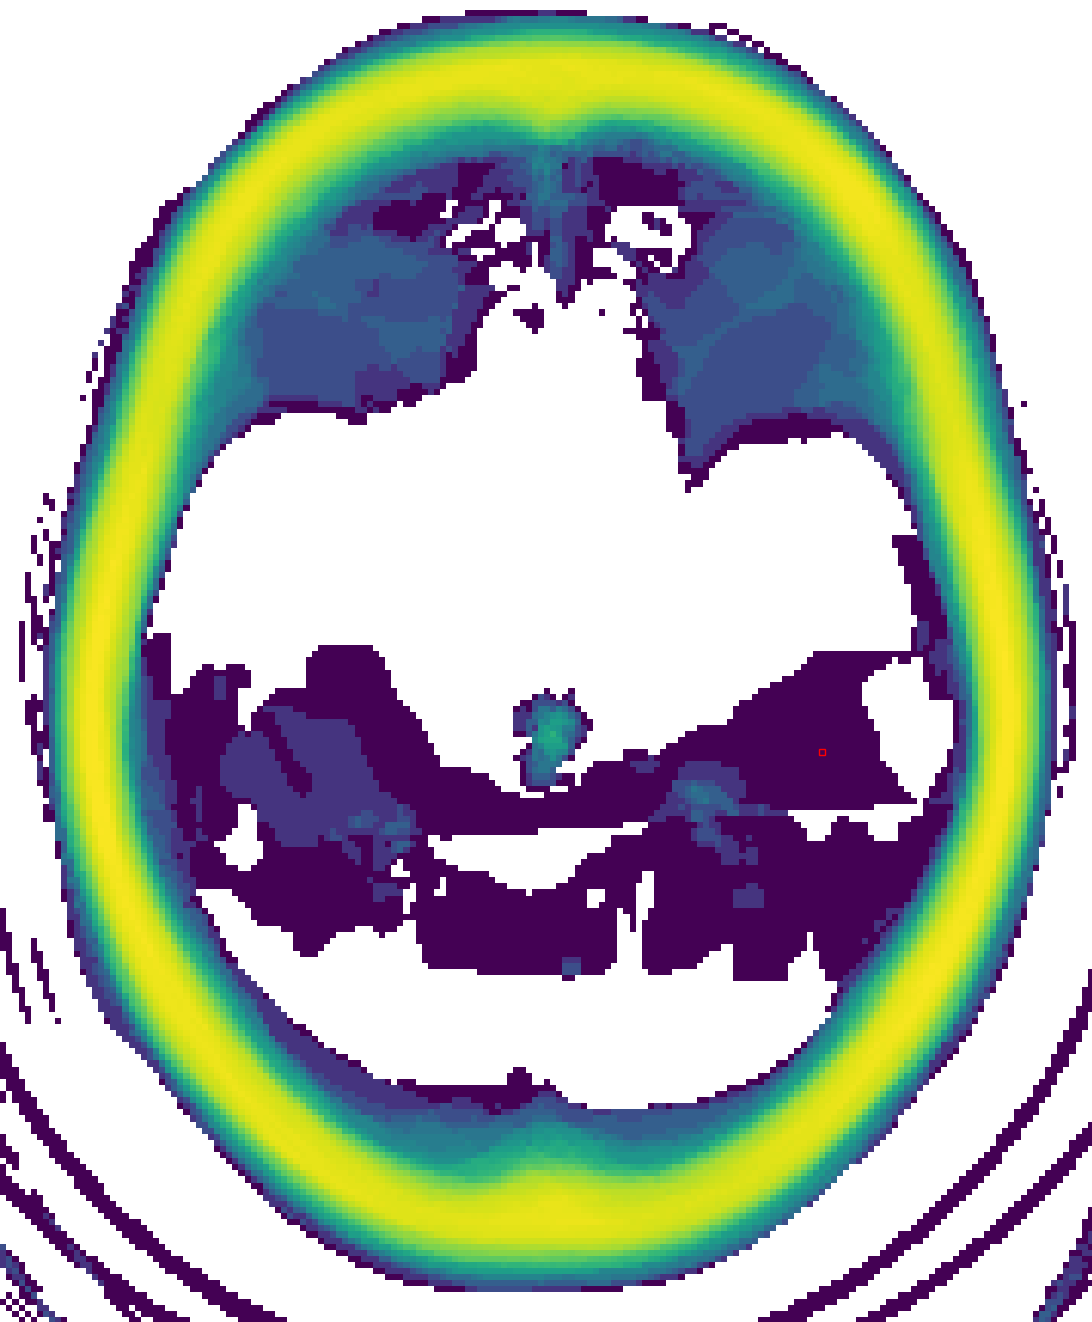

Comparing SSIM scores across CT series that cover different amounts and locations of the head is meaningless. Especially some older CT scanners produce separate series for the skull base and skull vault due to the need for different energies of radiation for each of these parts (modern scanners modulate energy delivery in real-time). We use the distribution of information presence over the z-axis in co-registered image sets to subgroup them into five categories: complete, skull base, medial, skull vault, and incomplete, before evaluating the similarity. We show exemplary cases of all subgroups except for the incomplete subgroup (as it is a collection of different types of series) in Figure 1.

We present the results from our proposed quality control methodology and our overall pipeline results. We summarise the information presence distribution of each subgroup with its median along the z-axis in Figure LABEL:subfig:group_information_presence, visualising the effectiveness of our proposed metric in classifying the series based on completeness. In Figure LABEL:subfig:information_presence_heatmap we depict the information presence distribution along the z-axis for the complete subgroup as a heat map (more in supplementary Figure 4), where the colouring denotes the number of series with the specific information presence at the specific slice (in log scale to make less frequent anomalies visible). We observe a wider spread of information presence in the lower slices (i.e., low values in the z-axis assuming standard orientation/positioning) due to differences in the starting position of the scanning and gantry tilt correction. While most series follow a hyperbolic curve from an information presence of about 0.6, peaking at about 0.75 and ending at 0, a larger group of series show higher information presence. These series exhibit relatively higher attenuation values inside compared to outside the scanner’s field of view, which can be masked by appropriate windowing.